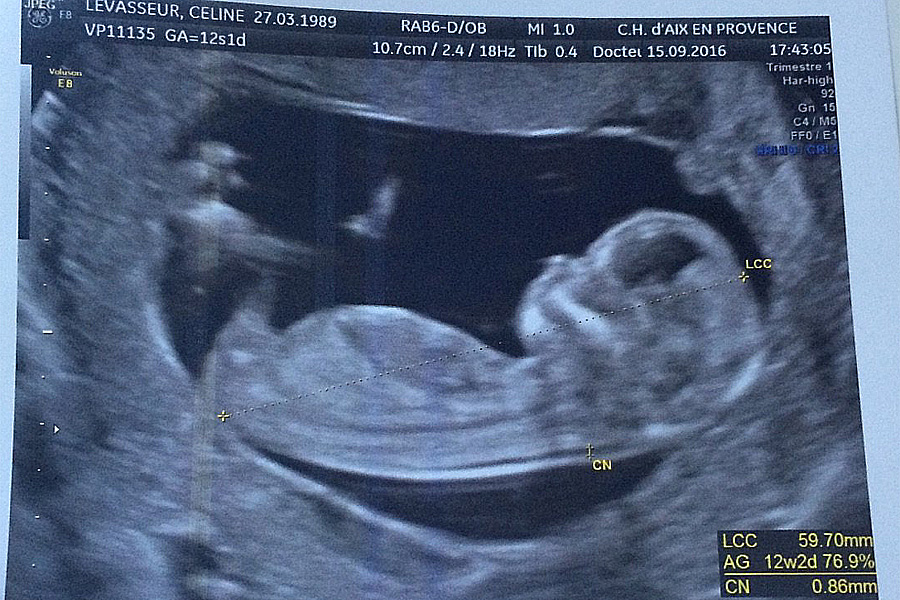

Le bébé de Céline...